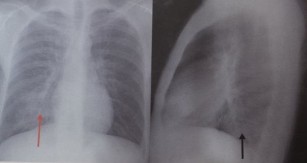

Pneumonia Interstițială Sau Atipică Pe Radiografia Toracică Proceduri Medicale